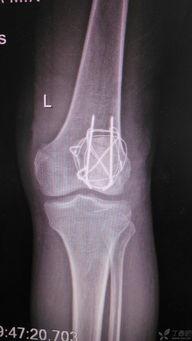

髌骨骨折康复训练视频,视频教程详解与康复步骤